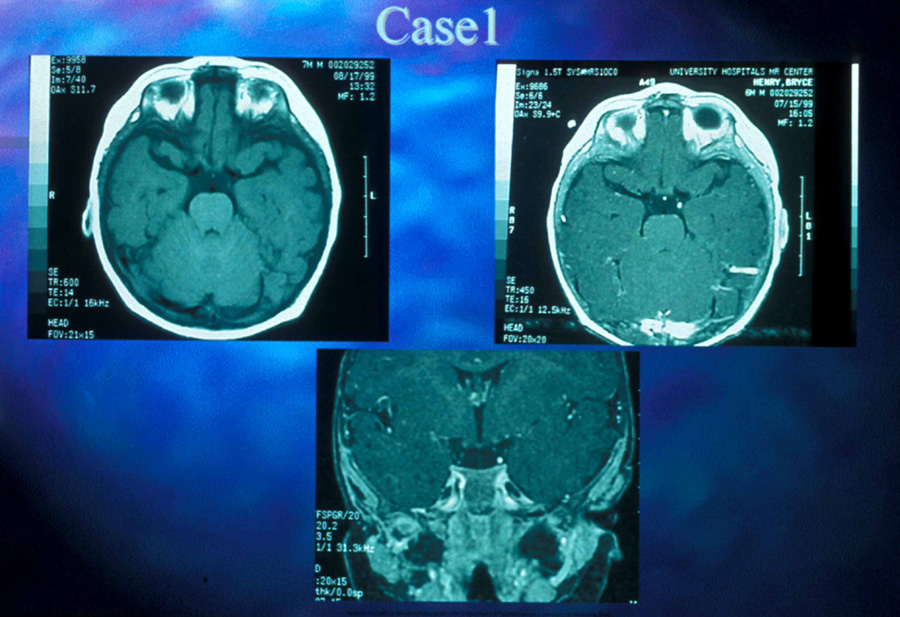

Anterior visual pathway gliomas account for the majority of intrinsic optic nerve tumors in childhood (Figs. 11, 12). Although they are true neoplasms, malignant features are extraordinarily rare in the pediatric population (see Chapter 5). Dutton58 provided a thorough review of this subject. When the glioma is initially confined to the optic nerve alone, the mortality rate is 5%. However, when the hypothalamus is involved, survival is less than 50% in some series. With a typically indolent course, these tumors generally can be managed conservatively, especially when confined to the optic nerve. Hoffman et al59 reviewed 62 cases of optic pathway/hypothalamic gliomas over a 14-year period, with 48 of these exhibiting relative stability with only visual defects: six patients had significant neurologic abnormalities, and eight died. Gayre et al60 reported a series of 42 patients with optic gliomas seen over 28 years at a single institution. Two-thirds were female, and slightly over half had neurofibromatosis type I (NF-1). Presenting signs and chiasmal involvement were similar in both NF (+) and NF (–) groups, the latter usually occurring within the first year after diagnosis. Regardless of treatment, the eye with better vision tended to remain stable over the long-term (and vision in the poorer eye often declined). Spontaneous regression of optic gliomas with visual improvement also has been reported.61,62

Fig. 11. Magnetic resonance imaging scans of optic gliomata. A. Marked enlargement of optic chiasm on coronal image. B. T1-weighted, gadolinium-enhanced image showing enlargement and marked enhancement of the right optic nerve and chiasm.